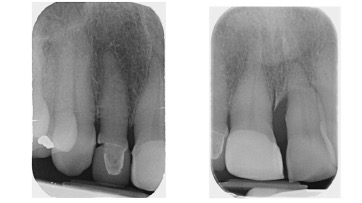

Crowns may be used to treat toothwear or broken down teeth. They are often selected where composite has failed, the teeth are too broken down or there is a need to provide a stronger material. This case was managed with surgical crown lengthening and multiple crowns. The lower incisors were treated with composite.